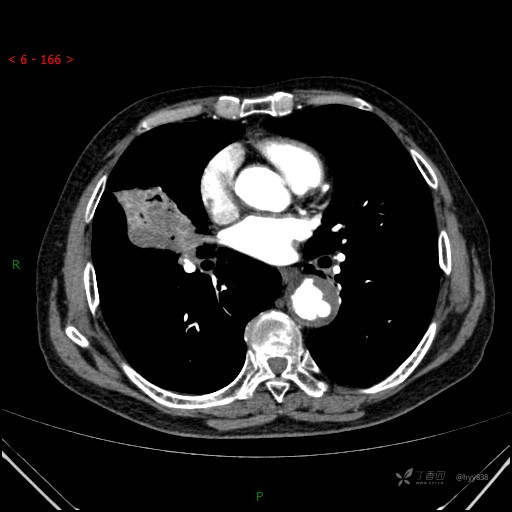

静脉期

增强动脉期